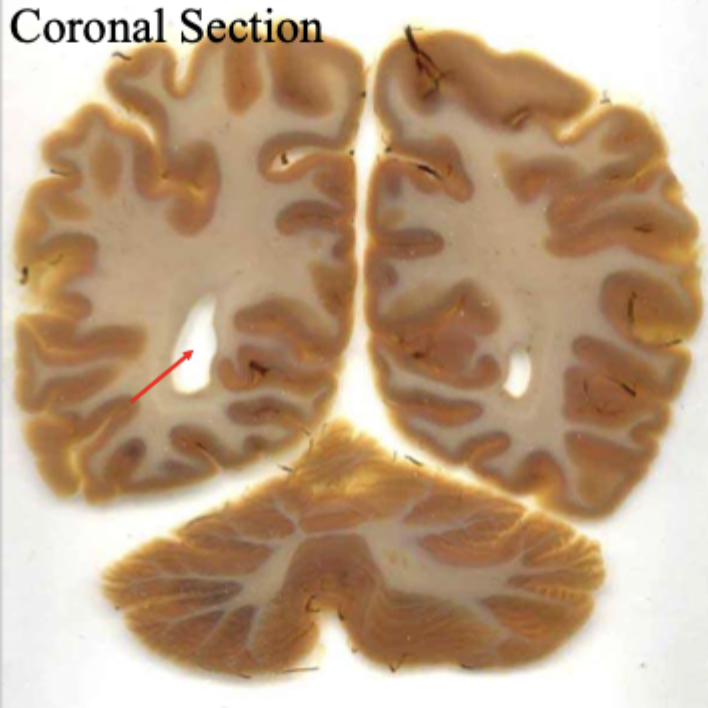

what slice of brain is this?

horizontal slice

coronal slice

What is the red arrow pointing to?

the anterior horn of the lateral ventricle